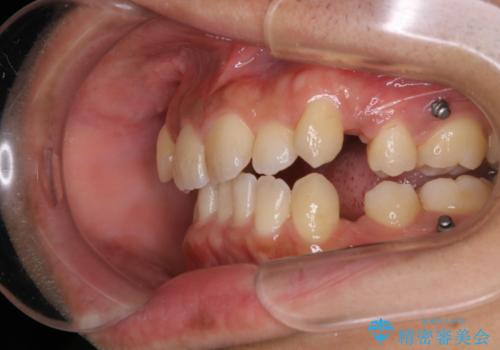

インビザライン単独でここまでできる!!抜歯矯正

- 治療計画

1日20時間以上、正しくインビザラインを使用して頂いたおかげで、ワイヤーに切り替えることなく矯正治療を終了することが出来ました。周囲からも歯並びがすごく綺麗になったと言われたのことで大変ご満足いただけました。